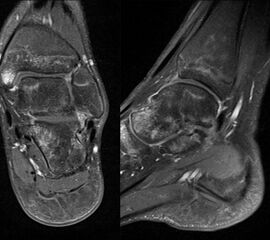

MRT

Die Kernspintomographie hat ihre Stärke in der Darstellung von Weichteilverletzungen. Insbesondere Verletzungen der Wachstumsfuge, des Periosts und der Bänder lassen sich gut visualisieren. Nachteilig ist die Untersuchungsdauer von 20-30 Minuten. Bleibt das Kind während dieser Zeit nicht ruhig liegen, kommt es zu Bewegungsartefakten, welche die Beurteilbarkeit der Bilder beeinträchtigen.

Fugengelenkfrakturen treten typischerweise vor dem 10. Lebensjahr auf, in einer Phase, in welcher die Wachstumsfugen noch weit offen sind. Dieser Frakturtyp betrifft fast ausschließlich den medialen Malleolus. Laterale Frakturen sind extrem selten, teilweise kommt es zu lateralen Bandverletzungen oder Fugenschaftfrakturen der distalen Fibula. Die Frakturlinie verläuft in einer Verlängerungslinie von der medialen Taluskante nach proximal. Häufig stellen sich Verletzungen des Innenknöchels im Röntgenbild schlechter dar, insbesondere wenn die Aufnahmen verdreht sind oder die Ebene der Fraktur bei geringer Dislokation verkippt zur Röntgenebene liegt. Besteht klinisch der geringste Hinweis auf eine Verletzung des Innenknöchels, muss aufgrund der Tragweite der Verletzung durch entsprechende Aufnahmen gegebenenfalls auch Schnittbildverfahren die Verletzung sicher diagnostiziert oder ausgeschlossen werden (Abb. 15).